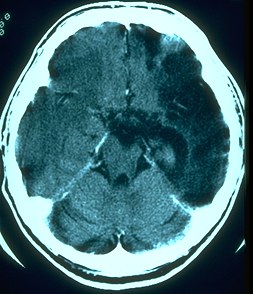

[Cat

Scan Hemorrhage]  [Cat

Scan Tumor]  CT (Computerized Tomography): 3-dimensional low energy x-ray scans of brain processed by computer